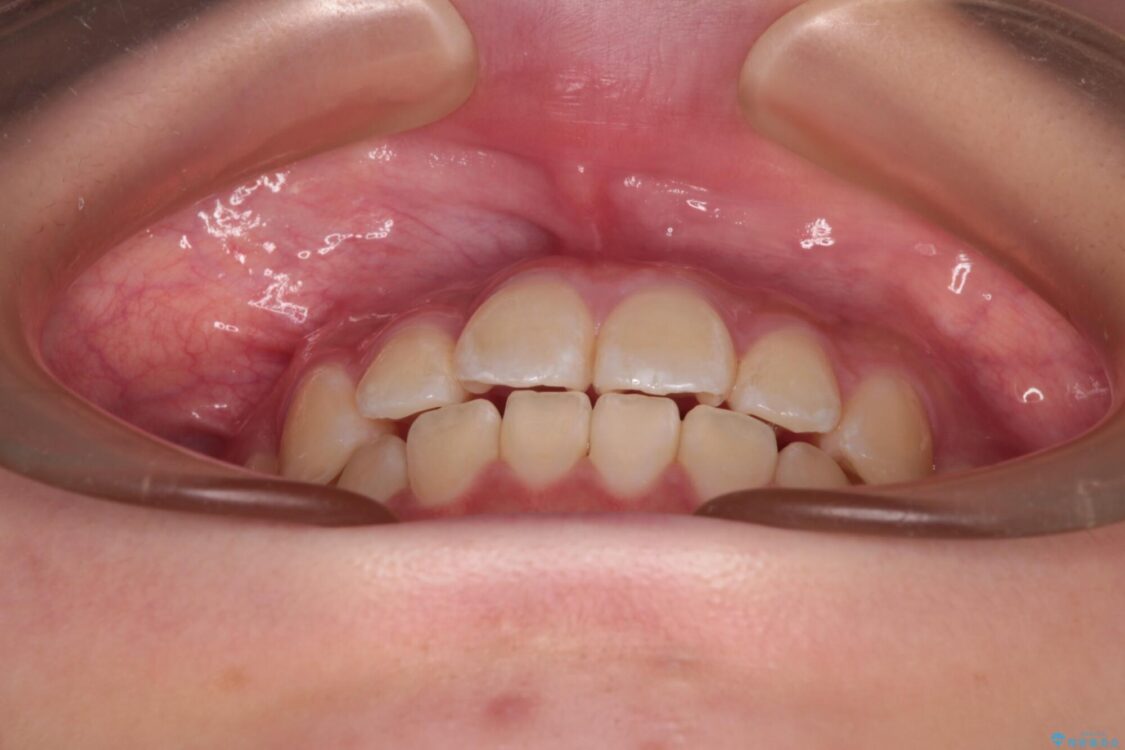

上下前歯のねじれを気にして来院された患者様です。

ワイヤー矯正でもマウスピース矯正でも対応可能でしたが、マウスピース矯正の自己管理が面倒であること、上顎前歯の捻転が著しいことから、ワイヤー矯正での治療を希望されました。

治療前

• インビザラインは使える自信がない ワイヤー装置にて矯正治療 治療前画像